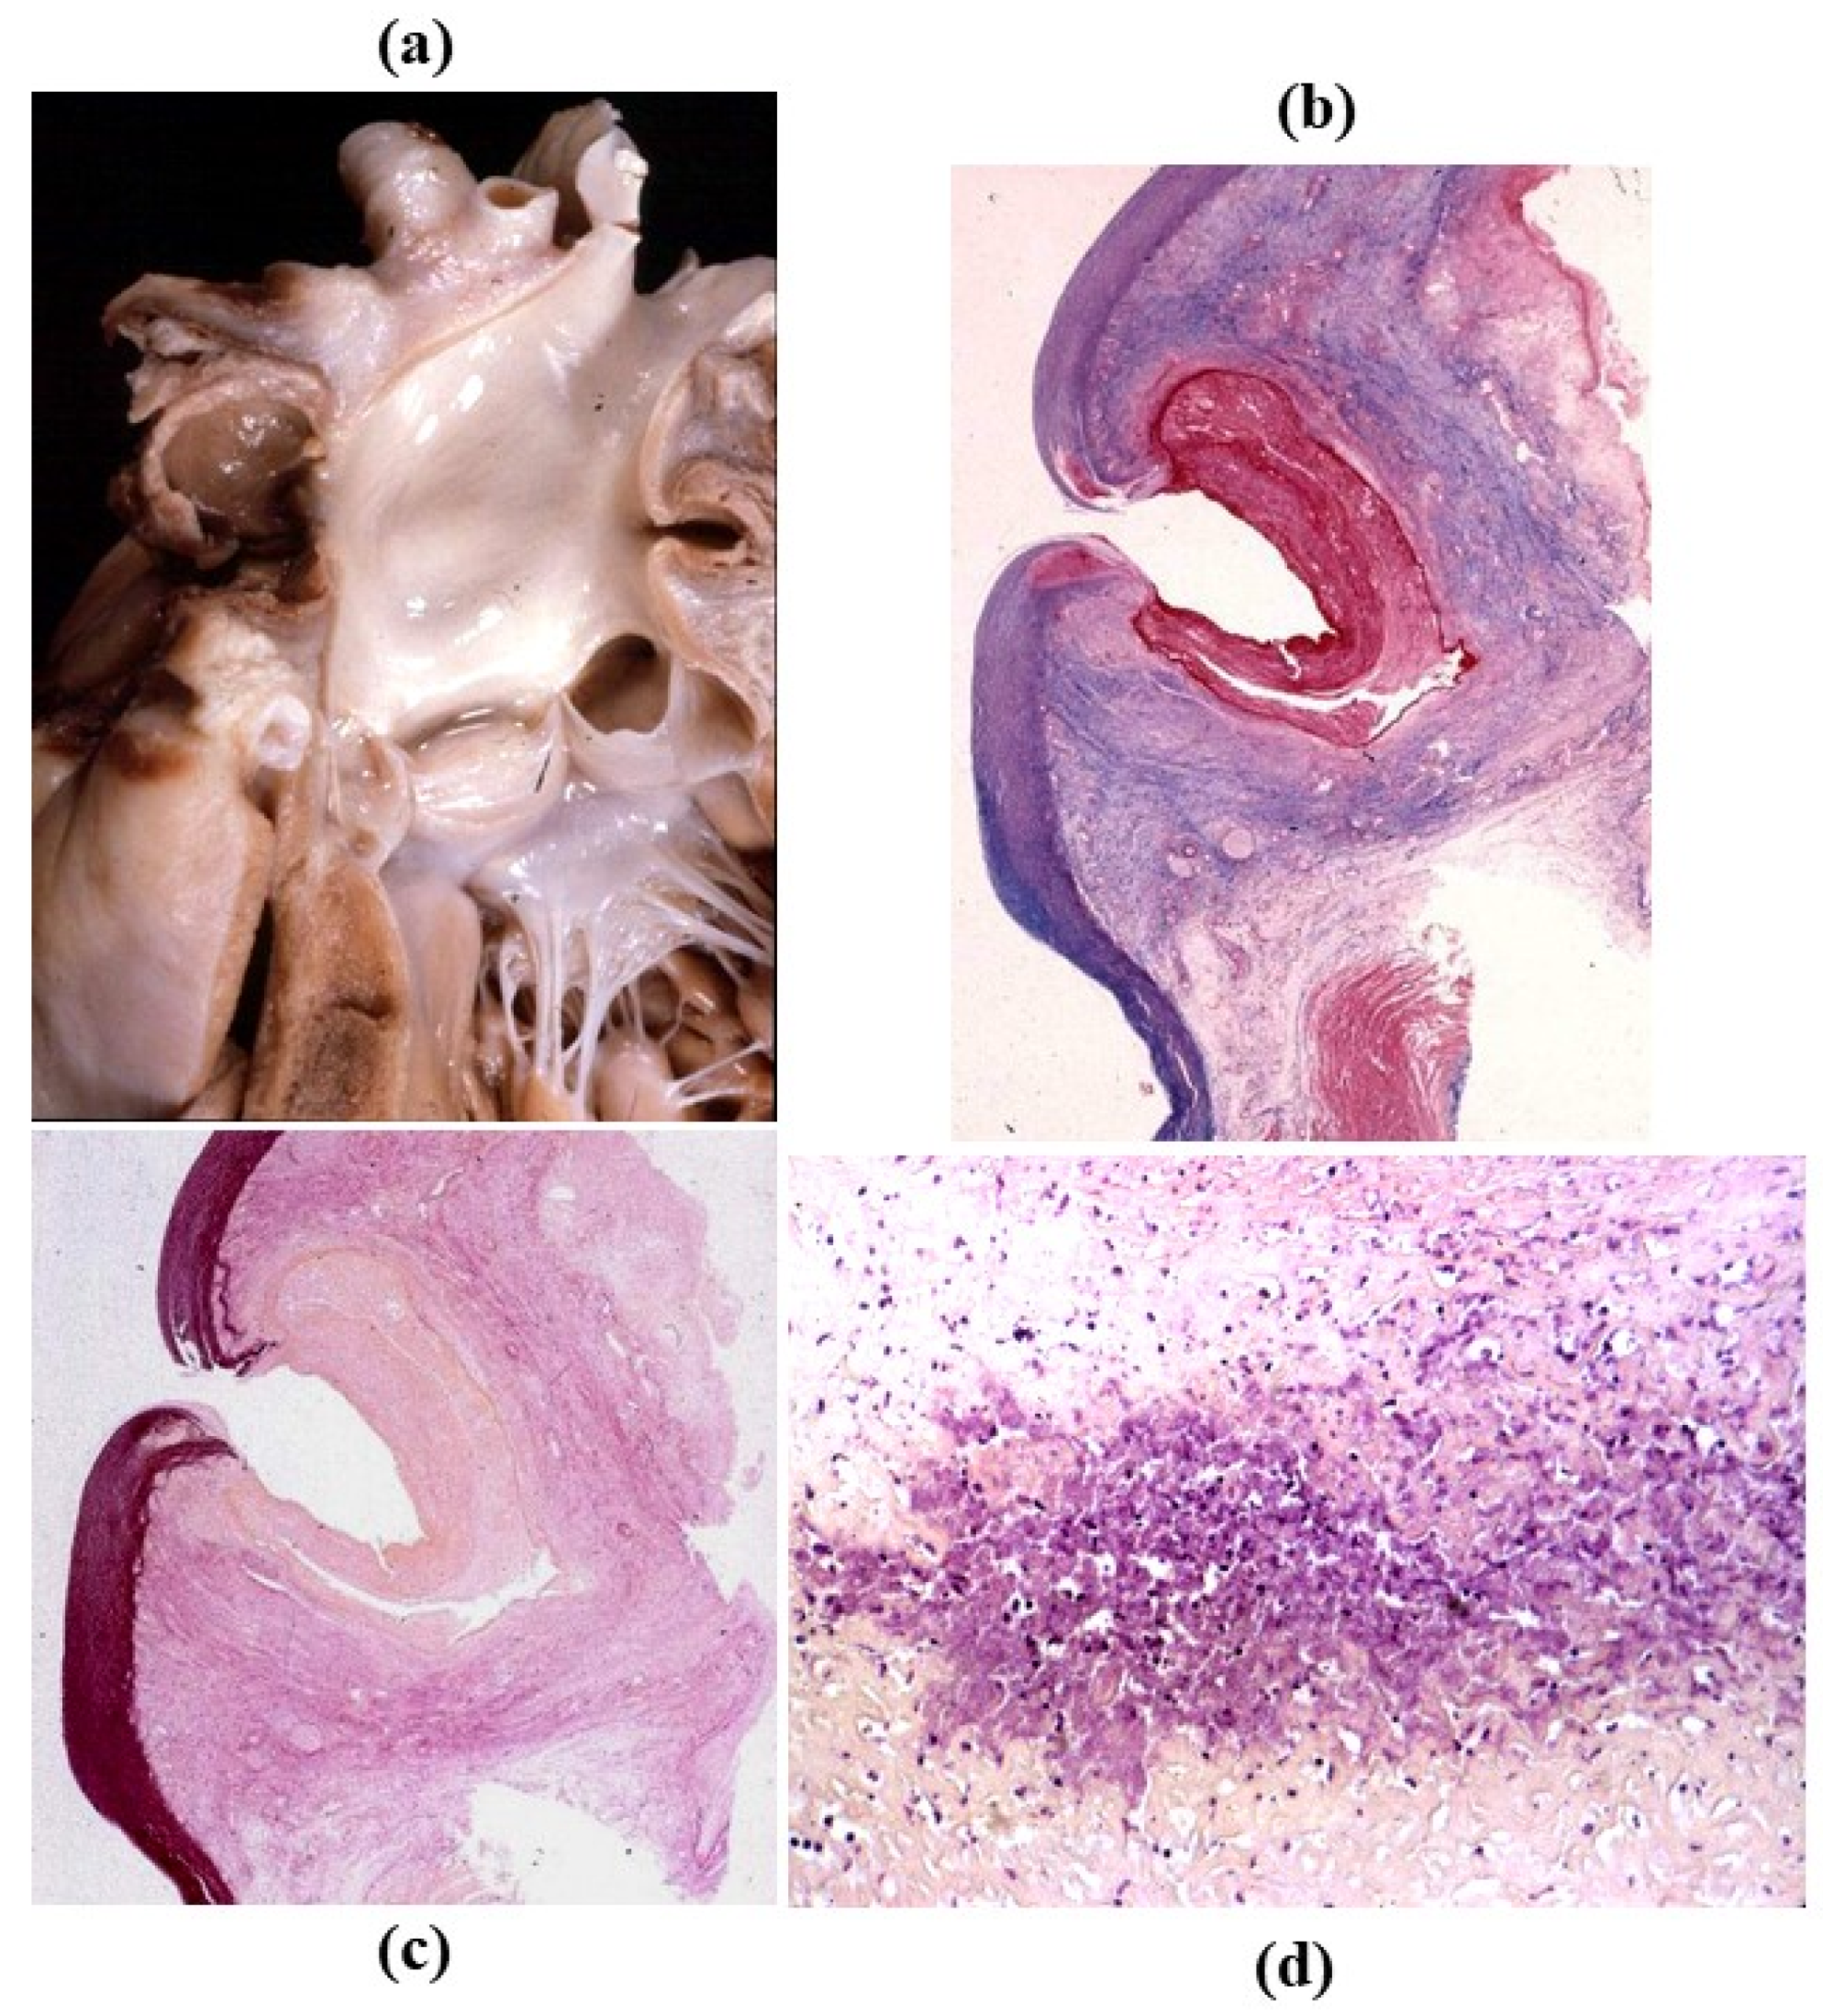

3.4. Inflammatory Diseases of the Aorta

- Cellular repopulation was observed in the outer part of implanted homograft wall by novel smooth muscle cells in the lamellar units (Figure 32a,b) and in the intima with a novel myointimal layer; this layer was noticed also in small animals such as rodents [68]. Novel endothelial cells appeared to line both the aortic wall intima and inflow/outflow at the cusp surface, as well as vasa vasorum, and valve spongiosa appeared repopulated by interstitial cells (Figure 32c,d);

- The ultrastructure of the wall revealed that novel smooth muscle cells have immature aspects, with a central oval nucleus, few contractile filaments and focal densities mainly located close to cytoplasmic membrane and in the paranuclear region; repopulated cells of the cusps are scarcely differentiated cells, in some case showing short intercellular junctions, rough endoplasmic reticulum and focal basal lamina (Figure 33), whereas others exhibited a fibroblast-like morphology;

- The undifferentiated nature of the repopulated cells is demonstrated by colocalization of some biomarkers. Novel wall cells showed positivity both for α-SMA and vimentin and novel cusp cells for SMA, vWF, VEGF, VEGF R2, α-SMA and CD57 (HNK-1), which is a neural crest marker;